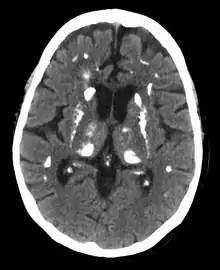

Common manifestations of hypercalcemia include weakness and fatigue, depression, bone pain, muscle soreness (myalgias), decreased appetite, feelings of nausea and vomiting, constipation, pancreatitis, polyuria, polydipsia, cognitive impairment, kidney stones ([nb 1]), vertigo and osteopenia or osteoporosis.[10][11] A history of acquired racquet nails (brachyonychia) may be indicative of bone resorption.[12] Radiographically, hyperparathyroidism has a pathognomic finding of rugger jersey spine.[13] Parathyroid adenomas are very rarely detectable on clinical examination. Surgical removal of a parathyroid tumor eliminates the symptoms in most patients.

Nuclear medicine

A technetium sestamibi scan is a procedure in nuclear medicine that identifies hyperparathyroidism (or parathyroid adenoma).[19] It is used by surgeons to locate ectopic parathyroid adenomas, most commonly found in the anterior mediastinum.